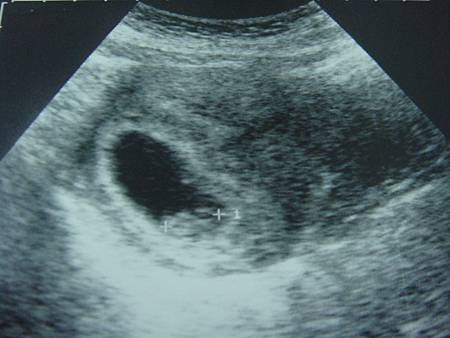

因為上禮拜還找不到88的存在 所以今天又來婦產科報到啦~~~

今天等好久..... 八點半等到九點多啊~~~